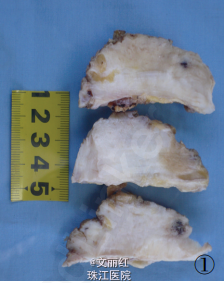

请糖尿病科会诊后,将血糖控制稳定后行肿物切除术。术中见肿物大小12*8*6cm,无包膜,切面实性,大部分为灰白色,质地硬。予以完整切除。冰冻提示良性病变。术后镜检:乳腺间质中含致密的胶原纤维似瘢痕样,小叶及导管周围件较多炎细胞浸润。病理诊断:糖尿病性乳腺病。